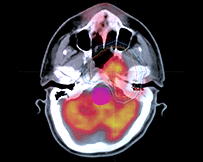

以往放射治療使用的都是強(qiáng)度幾乎一致的射線,而腫瘤本身的厚度是不均一的,因此造成腫瘤內(nèi)部劑量分布不均。為了實(shí)現(xiàn)腫瘤內(nèi)部劑量均勻,必須對照射野內(nèi)的射線強(qiáng)度進(jìn)行調(diào)整。

IMRT技術(shù)要求把一束射線分解為幾百束細(xì)小的射線,分別調(diào)節(jié)每一束射線的強(qiáng)度,射線以一種在時(shí)間和空間上變化的復(fù)雜形式進(jìn)行照射。

IMRT通過改變靶區(qū)內(nèi)的射線強(qiáng)度,使靶區(qū)內(nèi)的任何一點(diǎn)都能得到理想均勻的劑量,同時(shí)將要害器官所受劑量限制在可耐受的范圍內(nèi),使緊鄰靶區(qū)的正常組織受量降到最低。

IMRT比常規(guī)放療多保護(hù)15% ~20%的正常組織,同時(shí)可增加20% ~ 40%的靶區(qū)腫瘤劑量。

促使IMRT得以實(shí)現(xiàn)的最重要的技術(shù)突破是強(qiáng)大的計(jì)算機(jī)程序,這種高精度的放療技術(shù)使腫瘤放射治療跨入新時(shí)代。